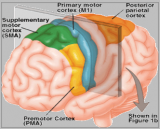

C'est un sous-domaine de la neuroscience qui se concentre sur l'étude des systèmes neuronaux complexes et de leur fonction dans le cerveau. C’est un réseau complexe de régions et de circuits cérébraux interconnectés qui travaillent ensemble pour exécuter des fonctions spécifiques liées à la cognition, au comportement et à la perception. Ces systèmes peuvent être considérés comme des modules fonctionnels responsables d'aspects spécifiques du traitement de l'information, tels que l'attention, la mémoire, le langage et les émotions. L'organisation de ces systèmes est très dynamique et peut changer au fil du temps en raison de l'apprentissage, du développement et de l'expérience. Les progrès des techniques de neuroimagerie, telles que l'imagerie par résonance magnétique fonctionnelle (IRMf) et l'électroencéphalographie (EEG), ont permis aux chercheurs d'étudier ces systèmes plus en détail, fournissant des informations sur la façon dont différentes régions du cerveau interagissent les unes avec les autres pour soutenir divers processus cognitifs.

Quelques exemples de systèmes de neurosciences bien connus incluent le système visuel, qui traite les informations visuelles des yeux, et le système limbique, qui est impliqué dans l'émotion et la motivation. D'autres systèmes incluent le réseau du mode par défaut, qui est actif pendant le repos et la pensée autoréférentielle, et le réseau de contrôle exécutif, qui est impliqué dans l'attention et la prise de décision. Comprendre l'organisation et la fonction de ces systèmes est essentiel pour développer des traitements efficaces pour les troubles neurologiques et psychiatriques, ainsi que pour faire progresser notre compréhension globale du cerveau et de l'esprit.